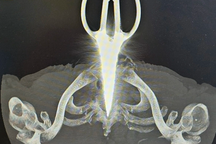

Bác sĩ thăm khám cho thấy bệnh nhân có khối áp xe ở vùng cổ nằm sau cơ ức đòn chủm phải và cạnh khí quản có một dị vật cản quang với biến chứng nguy hiểm.

Ngay sau đó, ông Đ. được phẫu thuật lấy mảnh dị vật có kích thước khoảng 1cm nằm cạnh khí quản.

Dị vật là mộc cây khoảng 1cm được lấy ra từ vùng cổ ông Đ. (Ảnh: CTV).